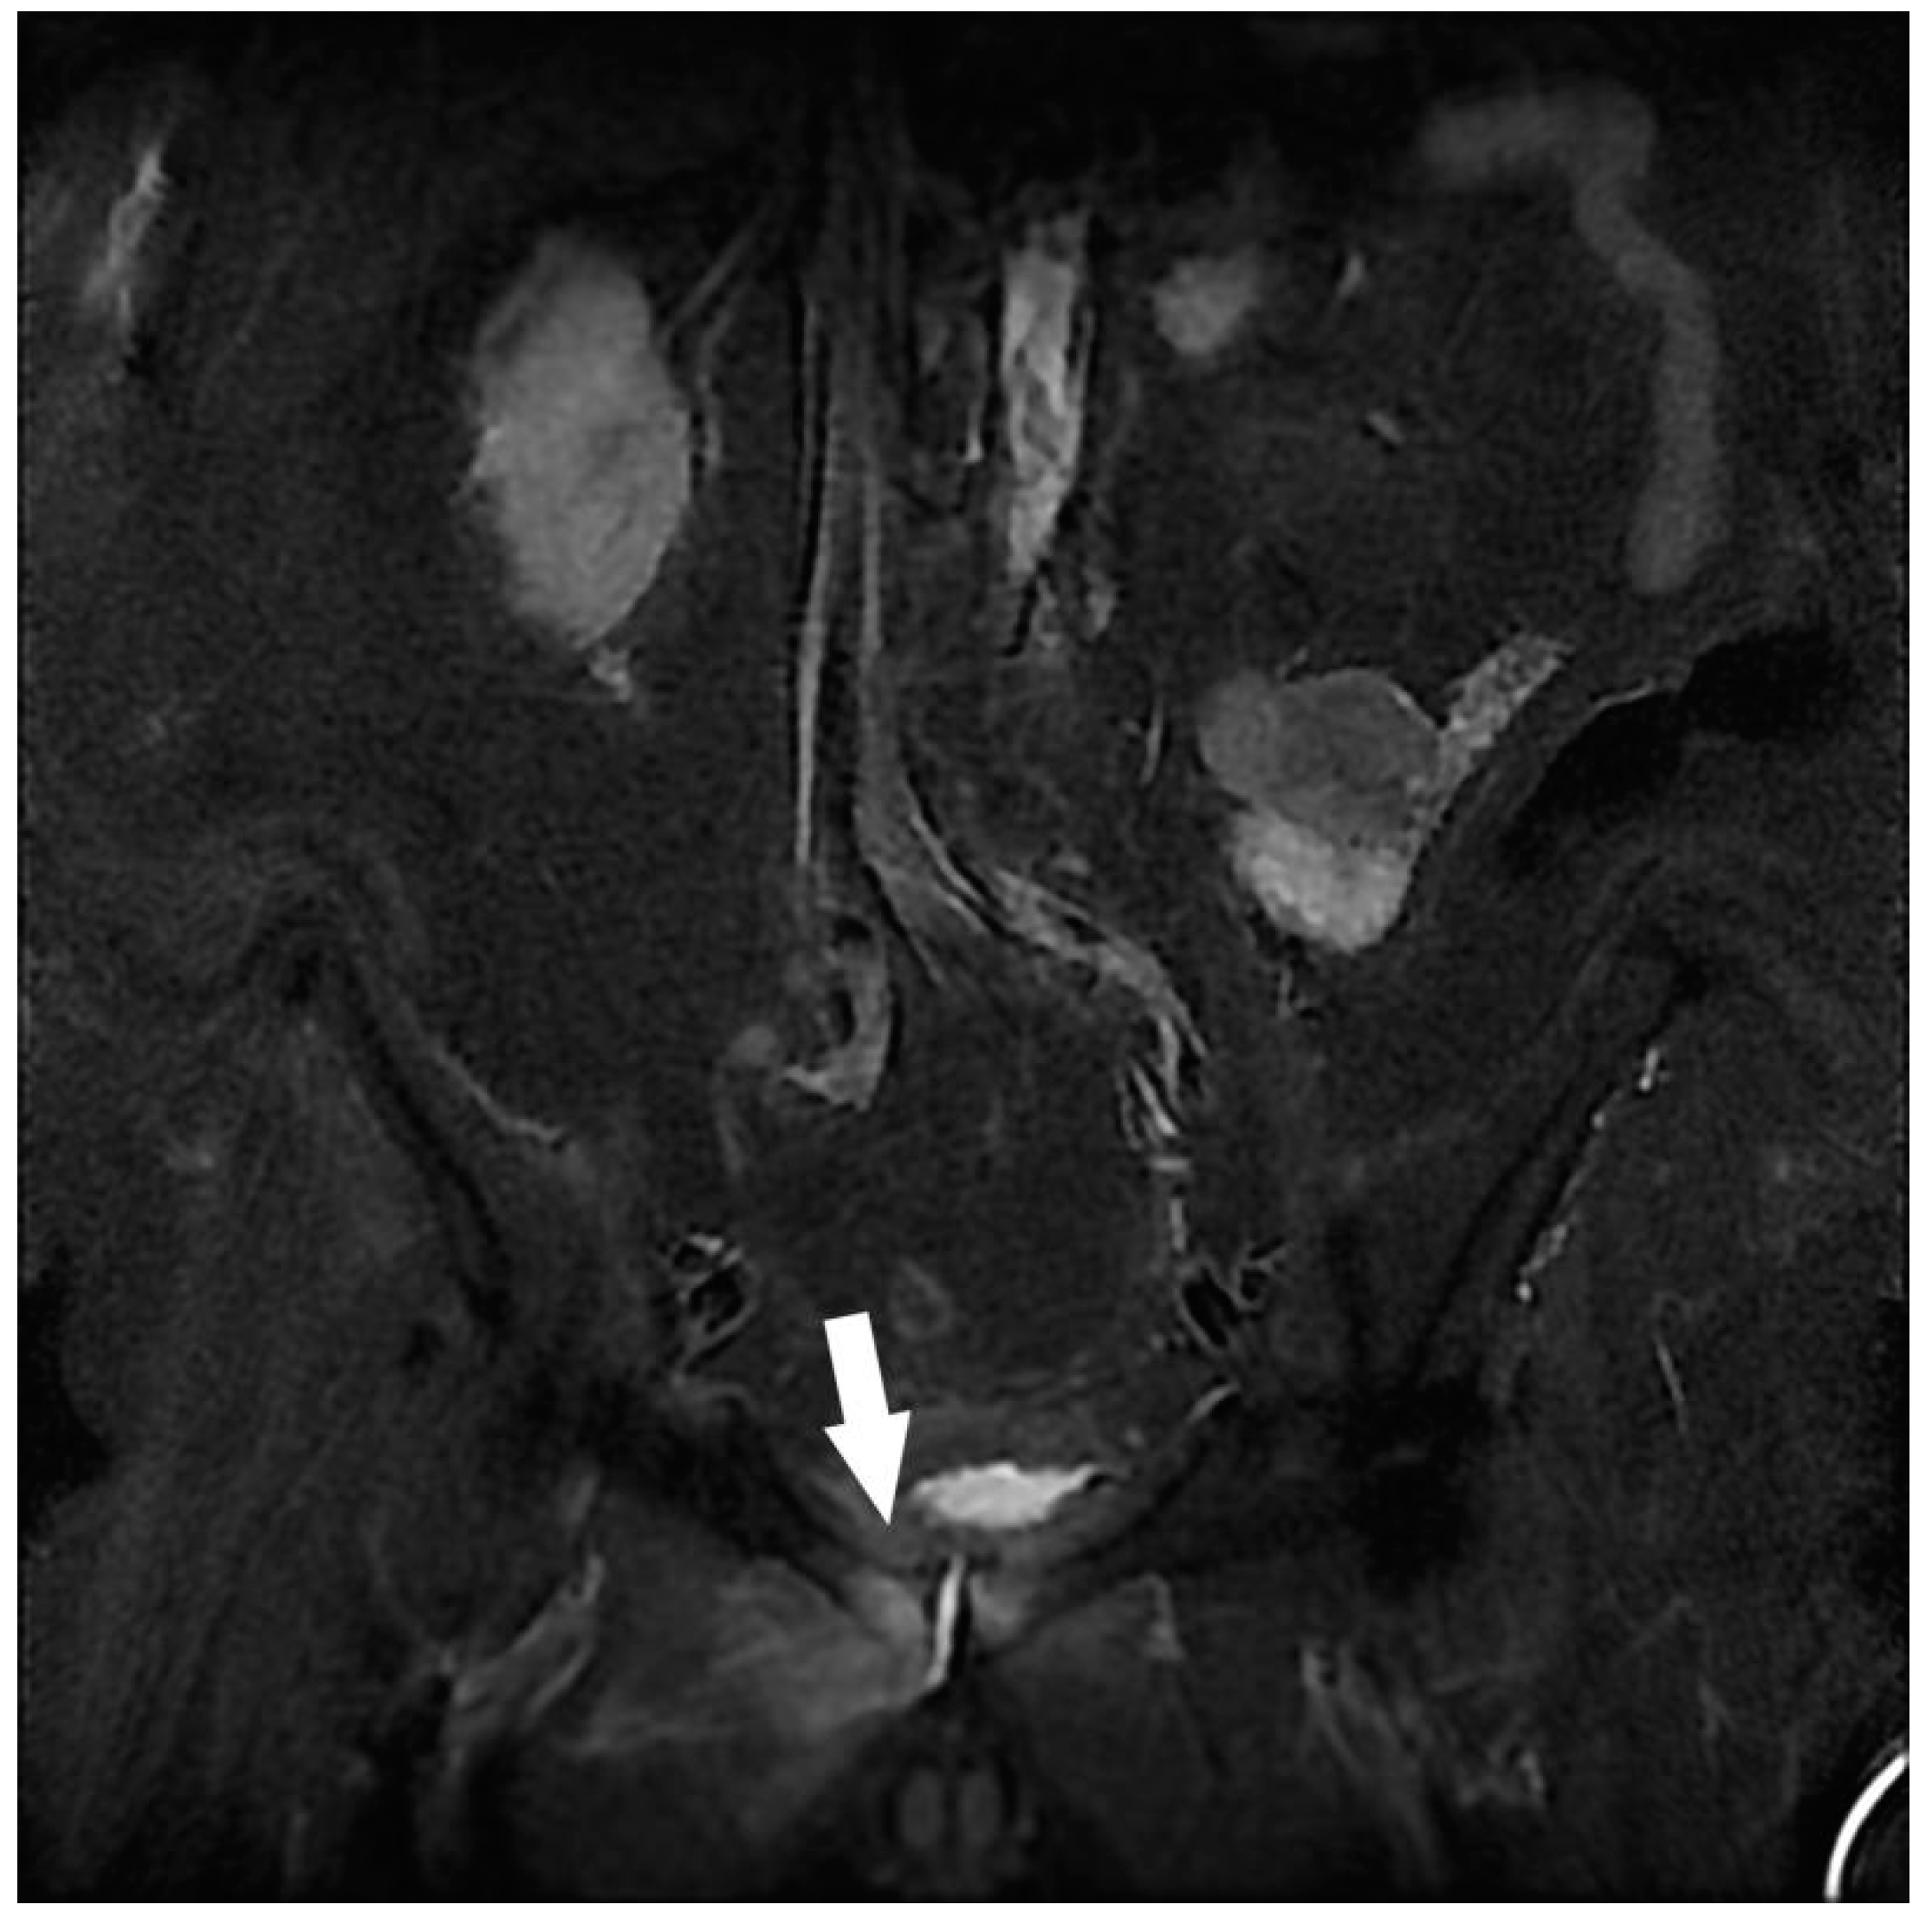

| Kidney | Atypical renal lesion 1 | 9 |

| Multicystic dysplasia, Polycystic kidney disease | 5 | |

| Liver | Non-cystic liver lesion 1 | 2 |

| Pelvis | Cystic or non-cystic ovarian lesion 1 | 15 |

| Prostatomegaly with struggle bladder | 11 | |

| Polymyomatous uterus | 4 | |

| Atypical uterine myoma 1 | 2 | |

| Indeterminate pelvic mass 1 | 1 | |

| Diffuse uterine adenomyosis | 1 | |

| Musculotendinous | Gluteal tendinobursitis 2 | 10 |

| Denervation edema on chronic root conflict 2 | 1 | |

| Intramuscular lesion (gluteus maximus) 1 | 1 | |

| Proximal iliotibial band enthesopathy 2 | 1 | |

| Osteoarticular | Congestive hip osteoarthritis 2 | 8 |

| Congestive degenerative sacroiliac arthropathy 2 | 8 | |

| Atypical bone lesion (iliac wing, femoral neck, sacrum) 1 | 3 | |

| Severe hip dysplasia 2 | 1 | |

| Congestive pubic osteoarthritis 2 | 1 | |

| Avascular femoral osteonecrosis 2 | 1 | |

| Others | Splenomegaly | 1 |